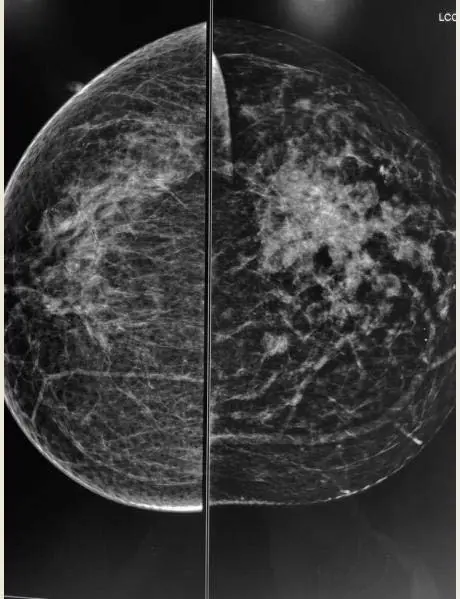

A & B) Left breast MLO and CC views showing irregular medium to high density mass in upper and outer quadrant of left breast ( straight white arrows) with associated interstitial thickening ( curved white arrow), ductal dilatation, skin thickening and retraction of the nipple (red arrow).

Left breast CC and MLO views

A) & B) Left breast CC and MLO view showing large asymmetric density in upper and central quadrant of left breast (black arrows) with associated interstitial thickening (white arrow) and architectural distortion .Multiple mass like areas seen in the medial and lower quadrant (red arrows) of left breast

• m/c mammographic finding Diffuse trabecular thickening and skin retraction.

• Can also present as an ill defined breast mass.

• Diffuse form - dense breast tissue with diffuse increase in skin thickness like inflammatory breast carcinoma

• Asymmetry between the breasts